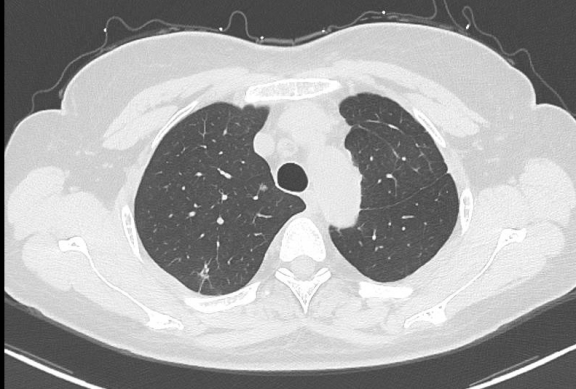

近日,广元市第一人民医院心胸血管外科团队勇闯高危手术“禁区”,成功为一位特殊的肺癌患者实施了Tubeless(无气管插管)自主呼吸麻醉下的单孔胸腔镜右肺上叶肿瘤切除术,最大程度减轻该患者双肺结节术后肺功能受损。该手术的成功开展,标志着医院胸外科微创技术及加速康复外科理念的应用迈上了新台阶,为心肺功能差、无法耐受传统单肺通气的复杂肺癌患者开辟了安全、精准、高效的手术新路径。

患者左肺上下叶均曾罹患肿瘤并接受过手术治疗,此次右肺上叶新发肿瘤,为其治疗带来了巨大挑战:

1. 肺功能储备严重受损:左肺已部分切除,肺功能基础差;

2. 无法耐受传统麻醉:传统的胸腔镜手术需要双腔气管插管进行单肺通气,但该患者因仅存的右肺也需要接受手术,且身体条件无法耐受单肺通气,这使得常规手术方案无法实施。

若放弃手术,患者将失去根治性治疗的机会。面对如此棘手的病情,心胸血管外科团队毅然决定迎难而上,经过多学科团队(MDT)的精密评估和充分讨论,最终为患者“量身定制”了国内领先的 Tubeless单孔胸腔镜手术方案。

所谓“Tubeless”,即术中不进行气管插管,在保留患者自主呼吸的喉罩通气全麻下进行手术。结合“单孔胸腔镜”技术,手术团队仅通过一个约3厘米的切口,便完成了右肺上叶肿瘤的精准切除。